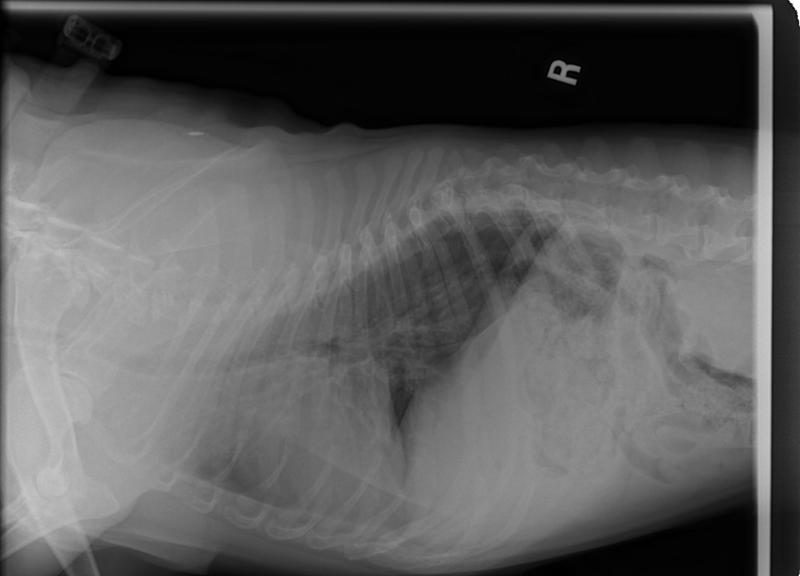

Even per his Vet at KAH, that he is on Baytril and, that he is battling these infections, is a bit concerning.

He has not had any incontinent issues since he was temp fostered as he is on the Baytril and that is wonderful news!!!